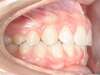

Cas 4 : Description

Chevauchement sévère. Traitement multibague sans extraction.

Avant

Après